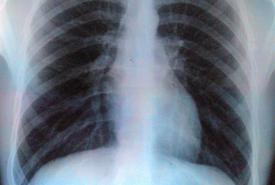

In AI, radiology finds a new ally

An artificial intelligence tool to interpret chest X-rays shows promise in Bengaluru trials Reading a chest X-ray is